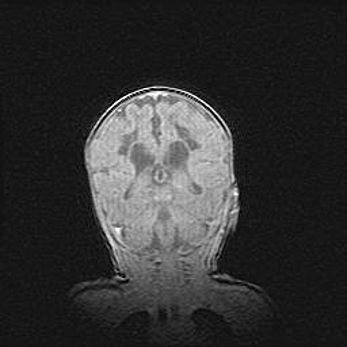

Церебральная ишемия II.

Возраст: 5 дней

Вес: 3400 г

Пол: женский

Окружность головы: 35 см

Срок гестации: 39 недель

Церебральная ишемия – это заболевание, характеризующееся недостаточностью (гипоксией) либо полным прекращением (аноксией) снабжения мозга кислородом по причине закупорки одного или нескольких сосудов. Это приводит к  что метаболическим расстройствам различной степени тяжести в тканях головного мозга, развитию коагуляционных некрозов и гибели нейронов.